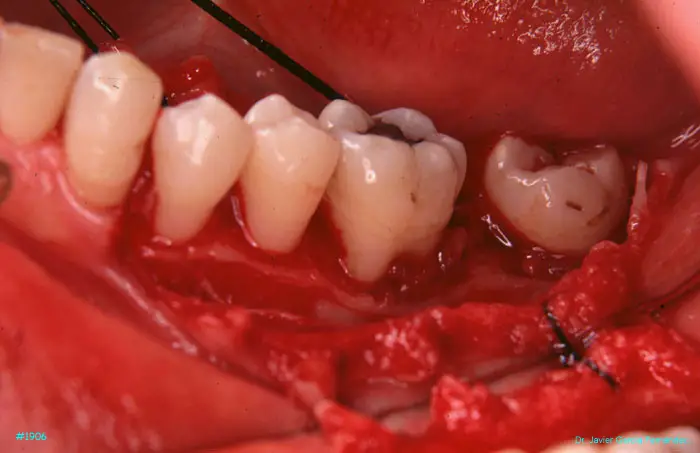

Atlas of Surgical Techniques in Periodontics. CASOS CLINICOS.

Atlas de Técnicas Quirúrgicas en Periodoncia

image 52